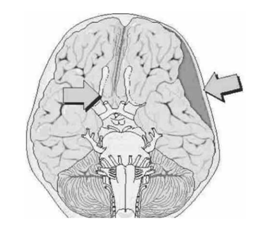

המטומה אפידורלית היא מצב שבו נוצר שטף-דם בין דורה לעצם הגורם ללחץ על המוח. בחבלות לטרליות בעיקר נפגע העורק Middle meningeal שהוא הגורם העיקרי להתפתחות המטומות אפידורליות (איור 3.16).

המטומה סובדורלית היא הסיבה השכיחה ביותר לצברי דם הנגרמים על ידי חבלת ראש. הסיבה לדמם היא קרע של כלי דם ורידיים המנקזים דם מהקורטקס או מהסינוסים הוורידיים שבדורה (איור 4.16). המטומות אלה יכולות להיות בתחילה א-תסמיניות או חלק ממצאים המלווים חבלה גולגולתית קשה המלווה בחוסר הכרה מידי, עם פרוגנוזה רעה, המתבטאת בשעורי תמותה גבוהים. ההמטומה יכולה להיות קטנה ולגרום לבצקת מוחית ניכרת בעיקר אצל צעירים, או להיות גדולה עם מיעוט תסמינים, בעיקר במבוגרים, בהם יש מרווח בין המוח לגולגולת ולכן גם המטומות גדולות יחסית יצרו מעט לחץ ומיעוט תסמינים. מחלקים את ההמטומות הסובדורליות בהתאם למרווח הזמן שחלף מהחבלה ועד הופעת התסמינים.